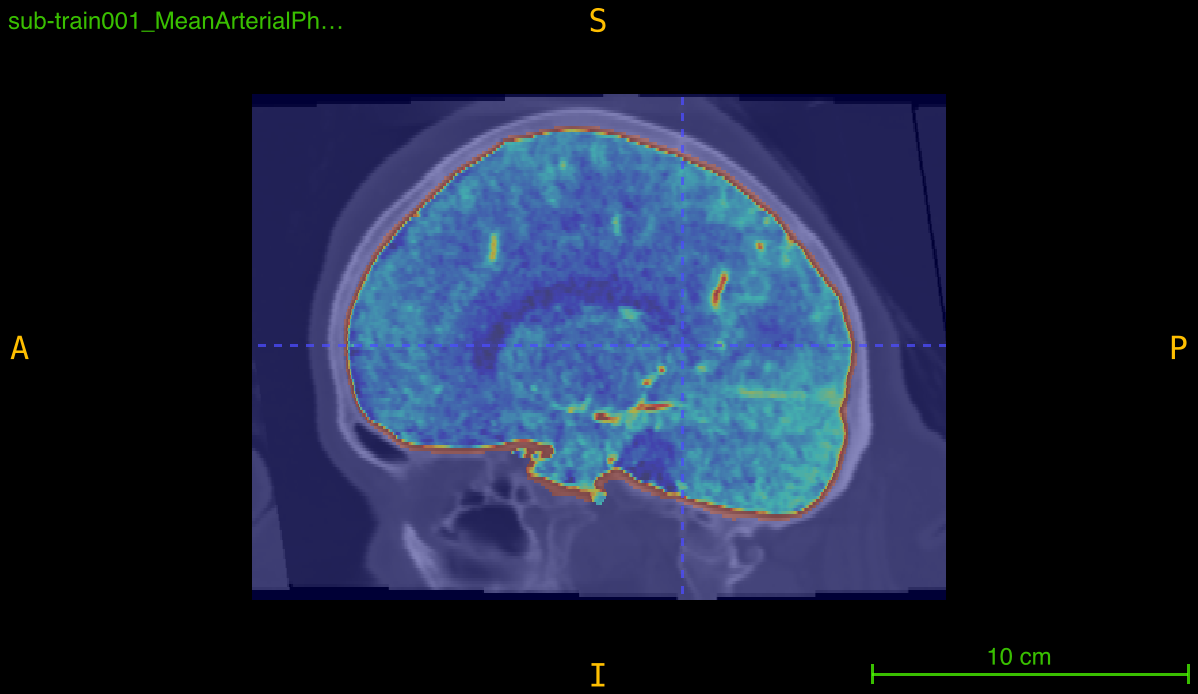

Apply a specialized skull-stripping pipeline to a single angiography volume using intensity preprocessing, Gaussian smoothing, and FSL BET for brain extraction.

This function implements a multi-stage skull-stripping pipeline specifically designed for contrast-enhanced angiography imaging. The pipeline combines intensity preprocessing with FSL’s Brain Extraction Tool (BET) to isolate brain tissue and vasculature from skull and non-brain structures.